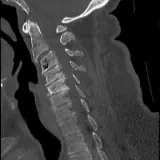

Over 2,100 interactive radiology cases, curated by radiologists for your level of training. Scroll, window, and view cases full screen — just like on PACS. Click linked findings in each writeup to jump straight to them on the image. Cases include sample reports, a focused discussion section, original illustrations, and videos.

PACSで期待されるツールを完備した完全インタラクティブな症例 — スクロール、ウィンドウ調整、ズーム、パン、計測、ROI、フルスクリーンモード。

重要な所見を症例画像上に直接ハイライトする豊富なアノテーション。症例解説内のリンクされた所見をクリックすると、スキャン上の正確な位置へジャンプできます。